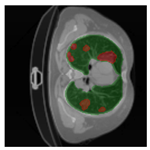

In Table 6, a comparison of the ground truth and prediction results of each model is presented in 2D, along with the 3D projection of each model. The visual analysis of the predictions provides additional insights into the performance of each model. The visualizations demonstrate that Attention UNet captures the intricate details of the lung construction more accurately, resulting in more precise segmentation of the infected areas compared to other models.

Table 6.

Comparison of ground truth and model prediction results using UNet, LinkNet, Attention UNet, UNet 3+, and TransUNet.